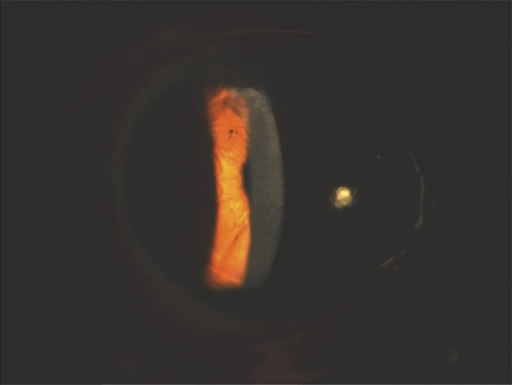

테리엔변연변성(Terrien Marginal Degeneration, TMD)은 각막 주변부의 비염증성 진행성 얇아짐으로, 주로 **상방(superior)**에서 시작하여 서서히 전주(circumferential)로 진행합니다. 30-40대 남성에서 흔합니다.

- 상방(superior) 주변부에서 시작

- 지질 침착(lipid arc): 중심측 경계에 황백색 선

- 표면 혈관신생: 주변부 신생혈관

- 진행성 얇아짐: 중심측은 급경사(steep), 주변측은 정상

- 상피는 intact (궤양 없음)

- 세극등: 특징적 소견